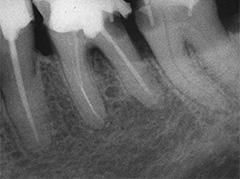

Als Zufallsbefund entdeckter, bis dahin beschwerdefreier apikaler Prozess an Zahn 36. Dessen insgesamt stark verengtes Innenraumsystem gestattete damals in erster Sitzung nur die Darstellung von 2 Kanälen. Wenn intensivstes Weitersuchen erfolglos bleibt, ist dem erfahrenen Behandler irgendwann zumindest so viel über den fehlenden Kanal bekannt: Er kann nicht sehr grosslumig sein und die Weitersuche auf den nächsten Termin zu verschieben ist nicht sehr riskant. Oft genug erlebt, gelingt dann frisch mindreseted und brainrebooted das in Sekunden, was zuvor in 20 min nicht gelingen mochte. So auch hier geschehen, bei der Suche nach dem 3. Kanal.

2 Aufnahmen sind von 2002 und die dritte vom 01.11.2010